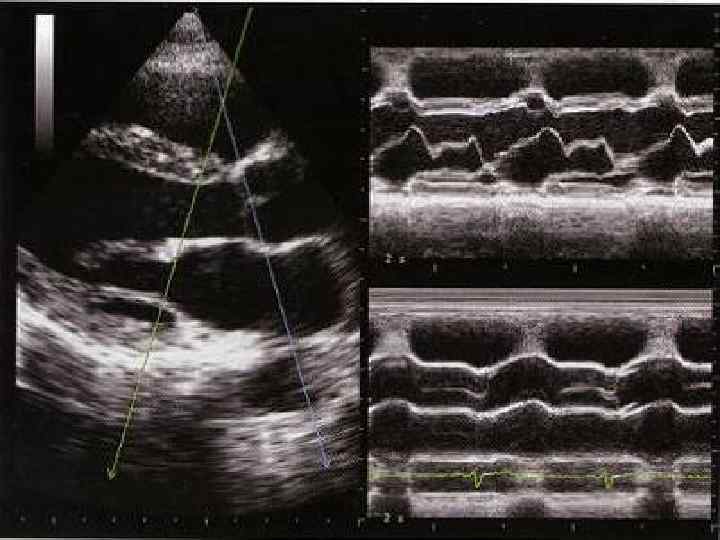

ОЦЕНКА СИСТОЛИЧЕСКОЙ ФУНКЦИИ ЛЕВОГО ЖЕЛУДОЧКА Систолическая функция ЛЖ оценивается по нескольким показателям, центральное место среди которых занимает ударный объем (УО) и фракция выброса (ФВ). Метод Teicholz. До последнего времени расчет УО, ФВ и других гемодинамических показа телей проводился на основании измерений М модальной эхокардиограммы, зарегистрирован ной из левого парастернального доступа. Для расчета учитывается степень передне заднего укорочения ЛЖ, то есть отношения КДР и KCР Расчет проводится по формуле L. Teicholz (где V объем ЛЖ (КСО или КДО) и D переднезадний размер ЛЖ в систолу или диасто лу. УО определяется как разница КДО и КСО, а ФВ — как отношение УО к КДО):

Нормативы стандартных измерений в парастернальной позиции 1. Диаметр правого желудочка в конце диастолы 25 38 мм (обычно менее 28 мм). 2. Диаметр LVOT или аортального фиброзного кольца 16 26 мм. 3. Диаметр аорты на уровне синусов Вальсальвы – 24 39 мм. 4. Аорта в области синотубулярного сужения 21 34 мм. 5. Левое предсердие 25 38 мм (в конце систолы). 6. Диаметр левого желудочка в конце диастолы и в конце систолы 37 53 мм (менее 56 мм), 23 36 мм. 7. Диаметр стенки правого желудочка в конце диастолы менее 5 мм. 8. Диаметр межжелудочковой перегородки в конце диастолы менее 12 мм. 9. Диаметр задней стенки левого желудочка в конце диастолы менее 11 мм.